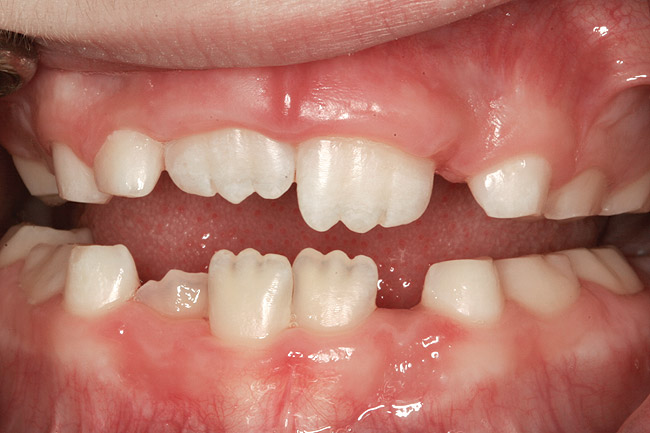

The point of obstruction tends to determine the type of skeletal impact. Nasal obstruction from enlarged turbinates, blocked ostium maxillare, deviated septum, or nasal valve stenosis creates Angle occlusions of Class I, II, and III equally (Figure 8). The maxilla in these cases is positioned posteriorly and the mandible is posterior-inferior. The facial type is most commonly dolicocephalic. Blockage of the airway predominately by the adenoids will create growth patterns that yield mostly Class II occlusions and anterior open bite with both jaws located posterior-inferiorly. Facial type is again dolicocephalic with the typical long-thin “adenoidal” face49 (Figure 9 through Figure 12). If the tonsillar tissue is responsible for the airway obstruction, the tongue will have an abnormal resting posture. Class III occlusions will be more common with the maxilla normal or posterior placed (Figure 13 through 15). The tongue may direct the mandible anteriorly or, because the tongue is not in the roof of the mouth driving A point anterior, the maxilla will become bimaxillary retrusive.50 In some cases, the anterior posture of the tongue will create an open bite. This is incorrectly referred to as a tongue thrust. The impact from a thrust does not alter the tooth position. Long-term, low forces cause tooth movement. The posture of the tongue against or between the anterior teeth due to the excessive tonsillar size creates the open bite (Figure 16 and Figure 17). Facial types in this group are more brachyfacial. Lastly, if the airway is blocked through a combination of factors, the Angle classification will be either Class II or III. The maxilla will be in a normal location and the mandible will be the affected arch (Figure 18). These craniofacial changes are not restricted to OSA; all SDB will create unique alterations depending on the patient compensation. Children with UARS have been reported to display high, narrow palates, dolicofacial form, and a Class II malocclusion, indicative of largely adenoidal blockage.51

(10.) Narrow maxilla with tooth wear and bilateral crossbite.

Figure 10

(12.) Class II Angle classification with worn dentition and anterior open bite.

Figure 12